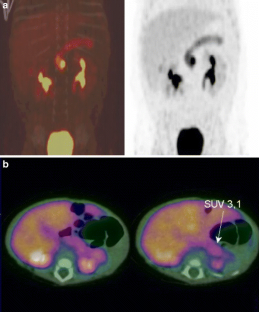

Congenital hyperinsulinism is a leading cause of severe hypoglycaemia in the newborn period. There are two (diffuse and focal) histological subtypes of congenital hyperinsulinism. The diffuse form affects the entire pancreas and if medically unresponsive will require a near total (95%–98%) pancreatectomy. The focal form affects only a small region of the pancreas (with the rest of the pancreas being normal in endocrine and exocrine function) and only requires a limited pancreatectomy. This limited section of the focal lesion has the potential for curing the patient. Thus the pre-operative differentiation of these two subgroups is extremely important. Recent advances in Fluorine-18-L-dihydroxyphenylalanine positron emission tomography (18F-DOPA PET/CT) have radically changed the clinical approach to patient with congenital hyperinsulinism. In most patients this novel imaging technique is able to offer precise pre-operative localisation of the focal lesion, thus guiding the extent of surgical resection.

Otonkoski T, Näntö-Salonen K, Seppänen M, Veijola R, Huopio H, Hussain K, et al. Noninvasive diagnosis of focal hyperinsulinism of infancy with [18F]-DOPA positron emission tomography. Diabetes. 2006;55(1):13–8.

Ribeiro MJ, De Lonlay P, Delzescaux T, Boddaert N, Jaubert F, Bourgeois S, et al. Characterization of hyperinsulinism in infancy assessed with PET and 18F-fluoro-L-DOPA. J Nucl Med. 2005;46(4):560–6.

Barthlen W, Blankenstein O, Mau H, Koch M, Höhne C, Mohnike W, et al. Evaluation of [18F]fluoro-L-DOPA positron emission tomography-computed tomography for surgery in focal congenital hyperinsulinism. J Clin Endocrinol Metab. 2008;93(3):869–75. Epub 2007 Dec 11.

Subramaniam RM, Karantanis D, Peller PJ. [18F]Fluoro-L-dopa PET/CT in congenital hyperinsulinism. J Comput Assist Tomogr. 2007;31(5):770–2.